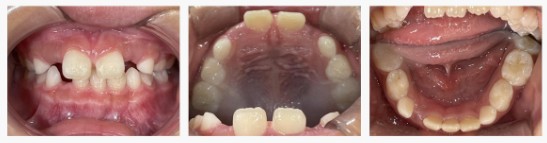

▼Before(治療前)

診察してみると、あごの成長に対して歯の大きさがやや大きく、**叢生(歯のガタガタ・重なり)**の傾向が見られました。

混合歯列期(乳歯と永久歯が混在する時期)は、あごの成長を誘導できる貴重なタイミング。

診断名は【叢生】